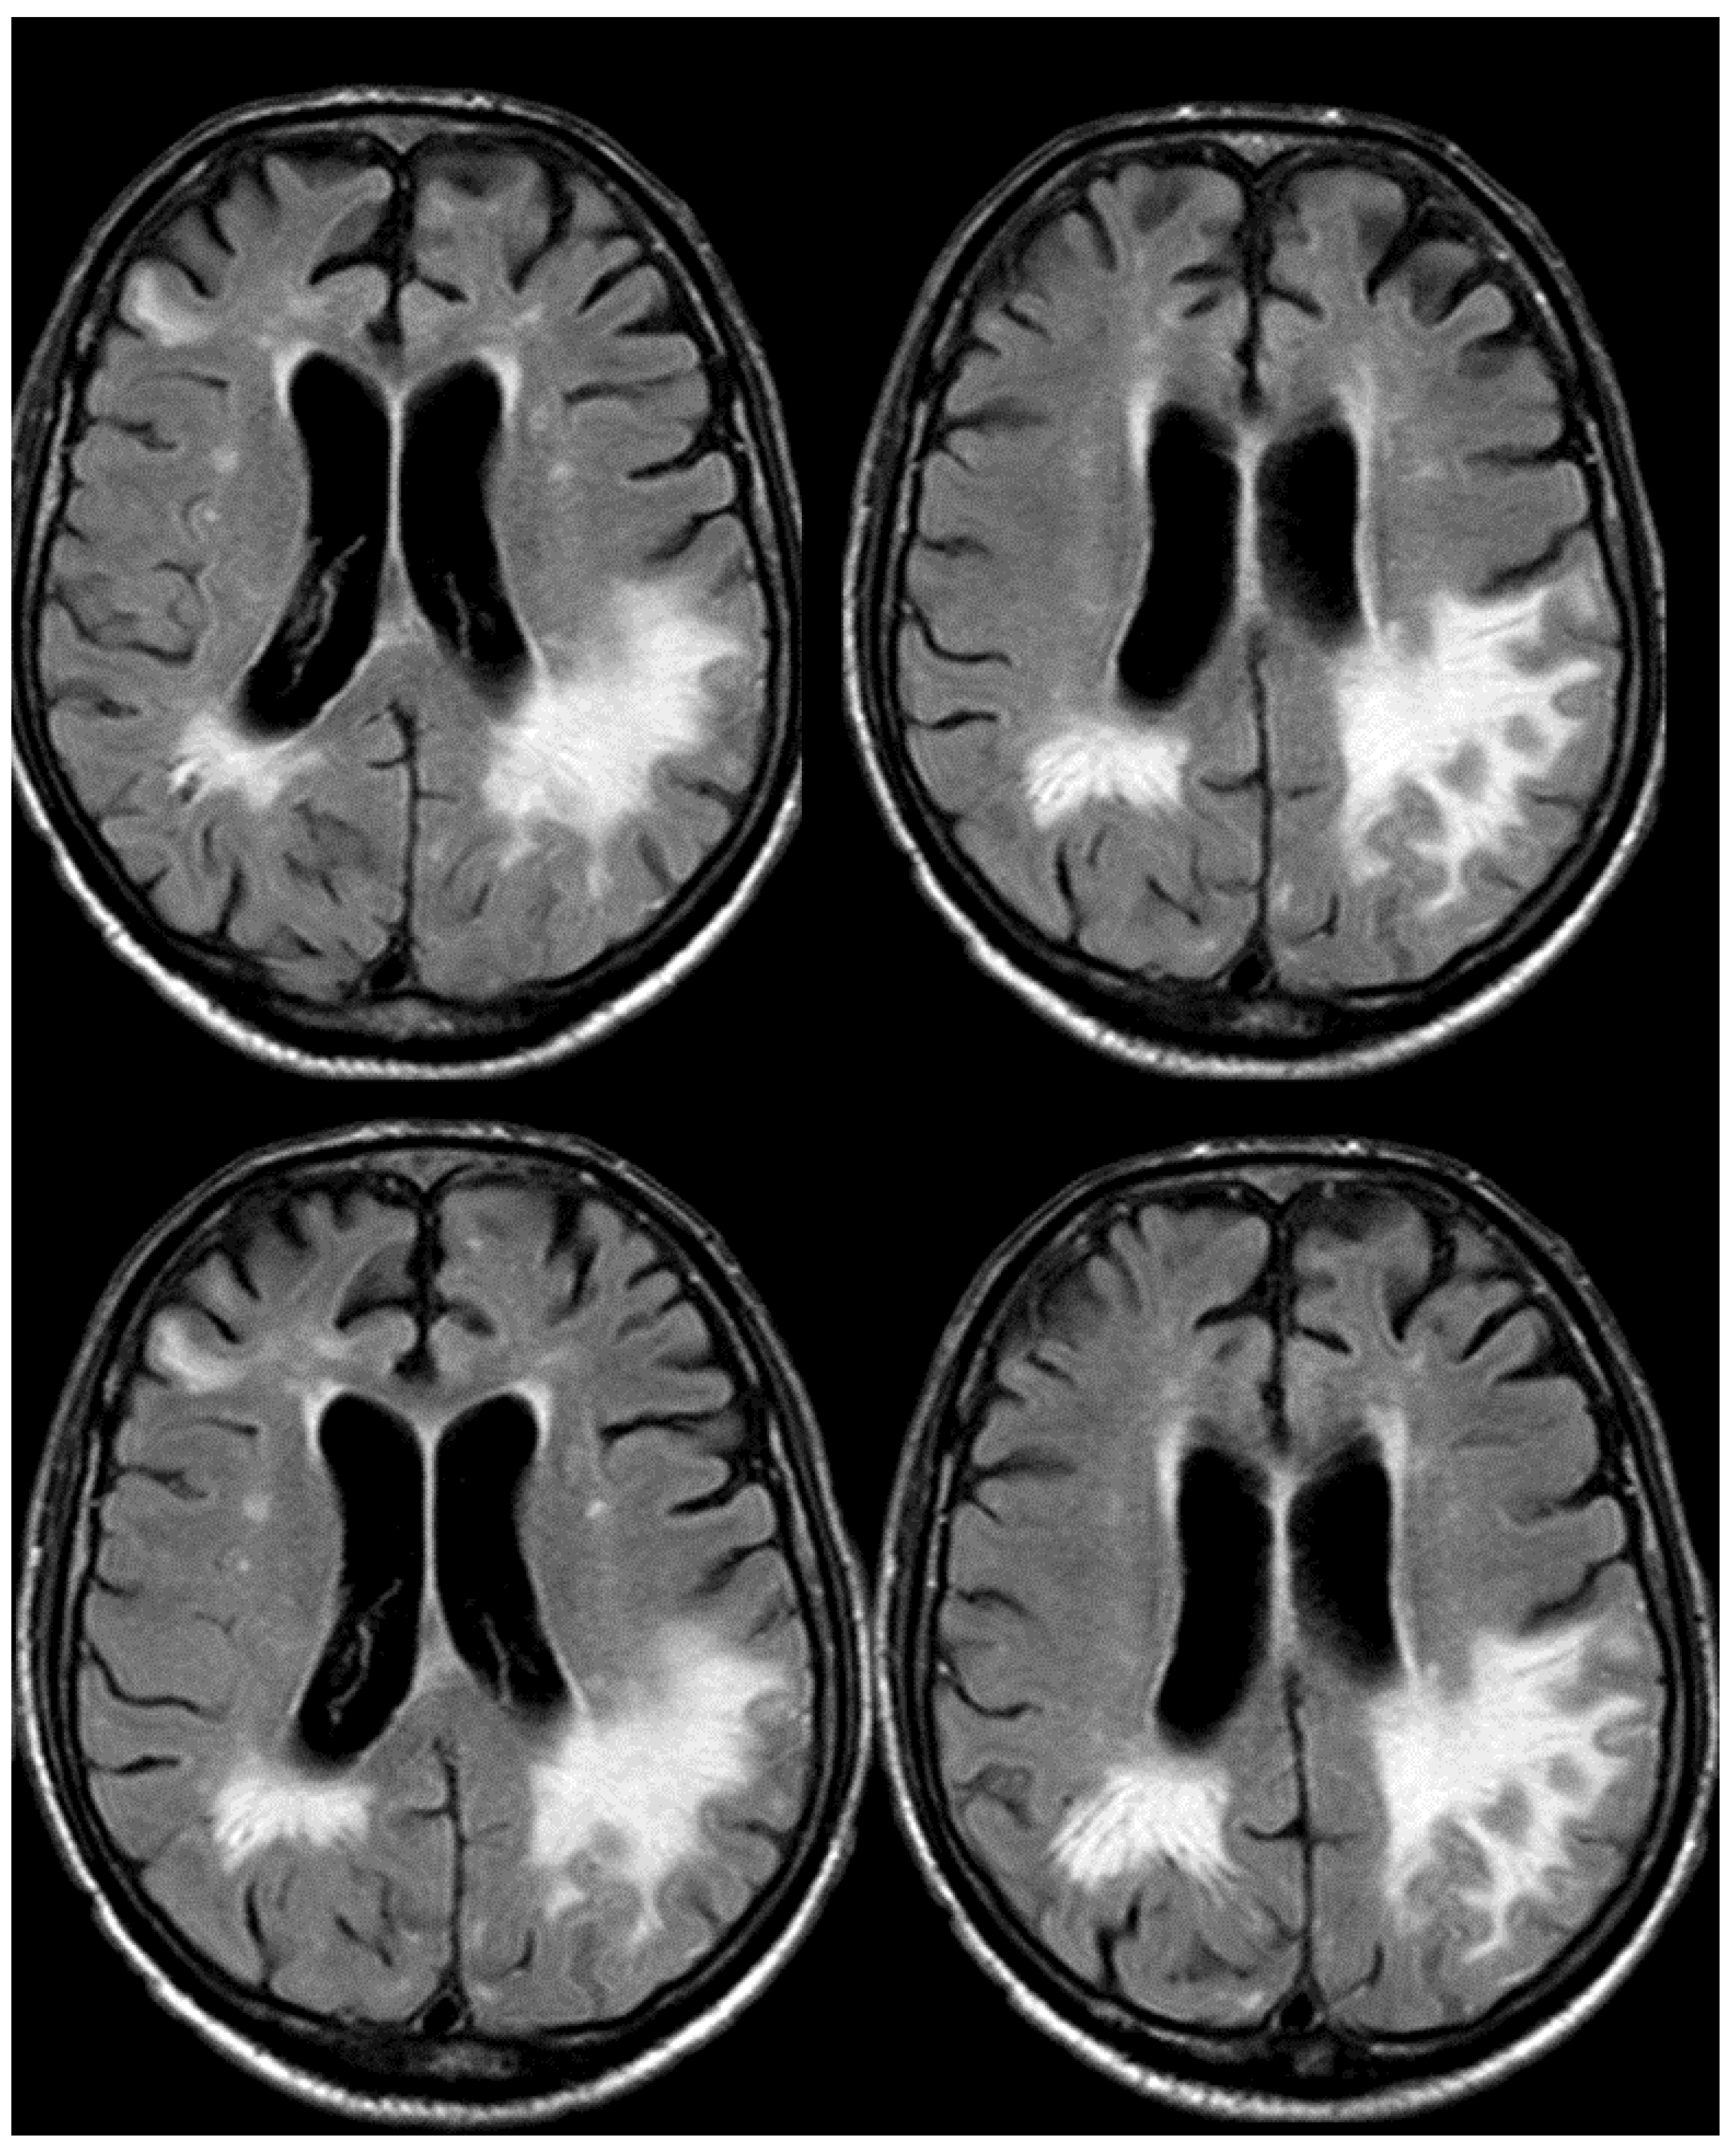

7. April 2018: Second Recurrent CAA-Related Inflammation

8. April 2018: Third Recurrent CAA-Related Inflammation